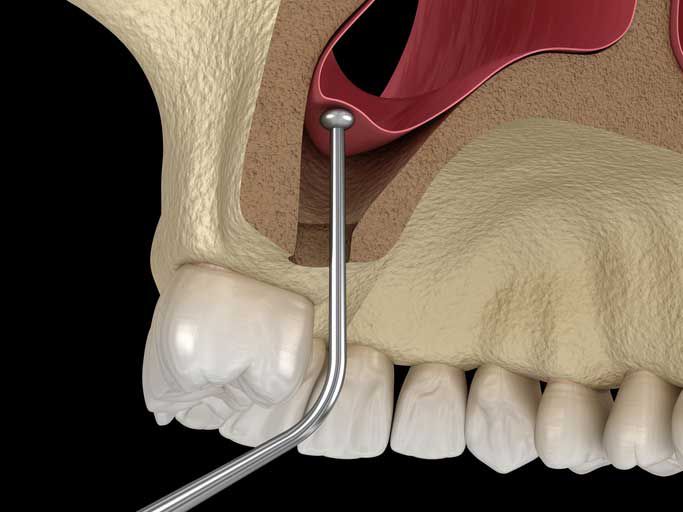

Resekcje

Te specjalistyczne zabiegi mają na celu zachowanie zęba w jamie ustnej, mimo występowania zaawansowanych procesów chorobowych. Dzięki nim możliwe jest usunięcie tylko chorej części zęba, pozostawiając zdrowe fragmenty w jamie ustnej.